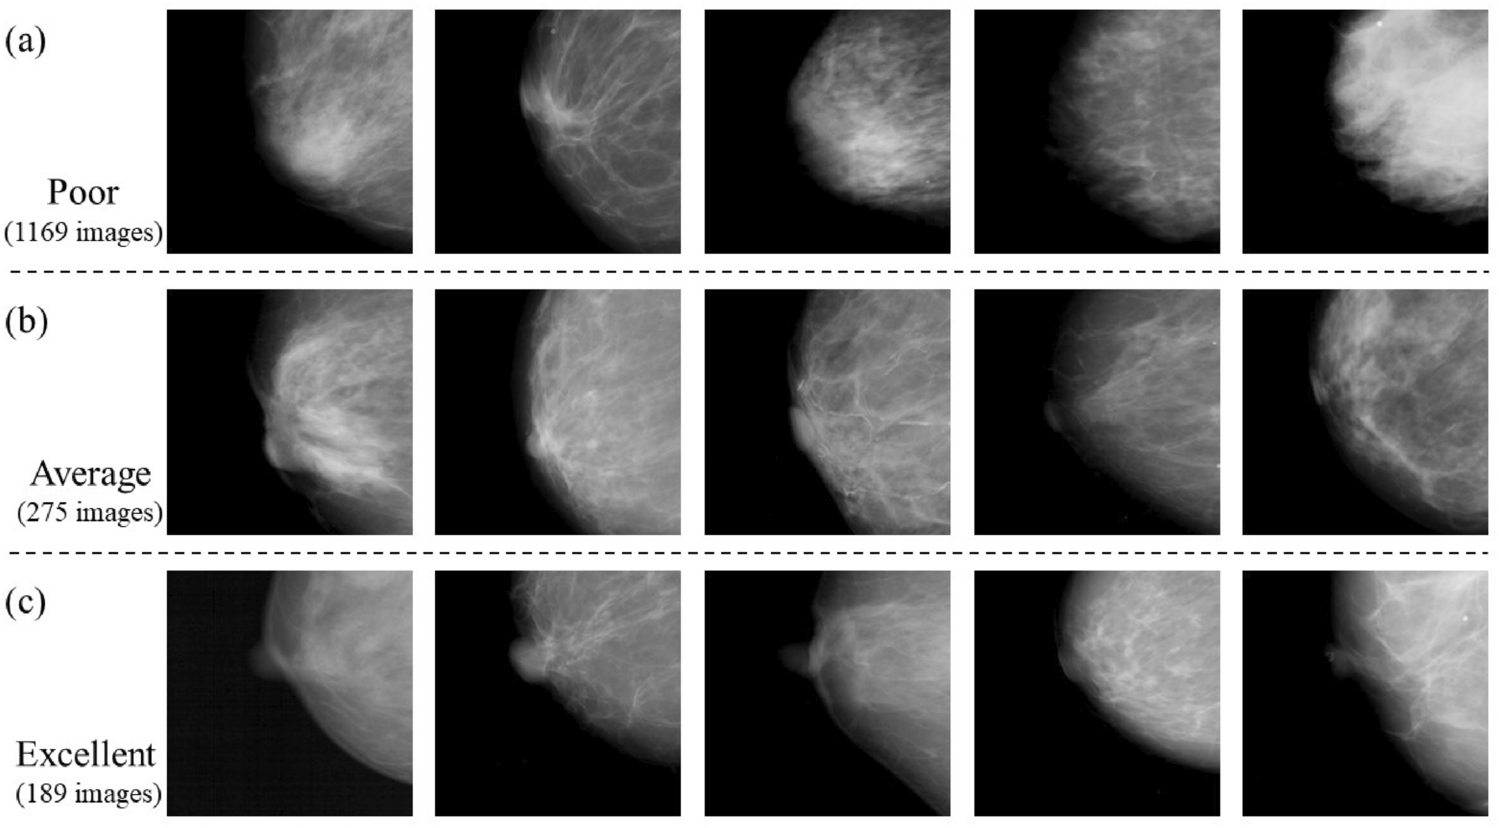

Figure 7

From: Quality control system for mammographic breast positioning using deep learning

Examples of learning and test images of the nipple classified into three levels: poor, average, and excellent. (a) Images labeled poor; (b) images labeled average; and (c) image labeled excellent.